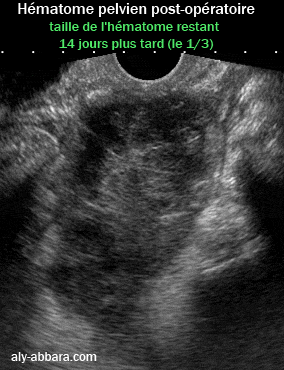

Image échographique montrant un hématome situé dans le pelvis ; il s'agit d'une complication post-opératoire suite à une hystérectomie totale par voie abdominale. |

L'image superposée montre la taille de cette hématome 14 jours plus tard. La surface occupée sur l'image par l'hématome à J14 est égale au 1/3 de la surface par le même hématome à J0. Cette différence donne une idée sur la vitesse de la résorption des hématomes de dans cette localisation. |